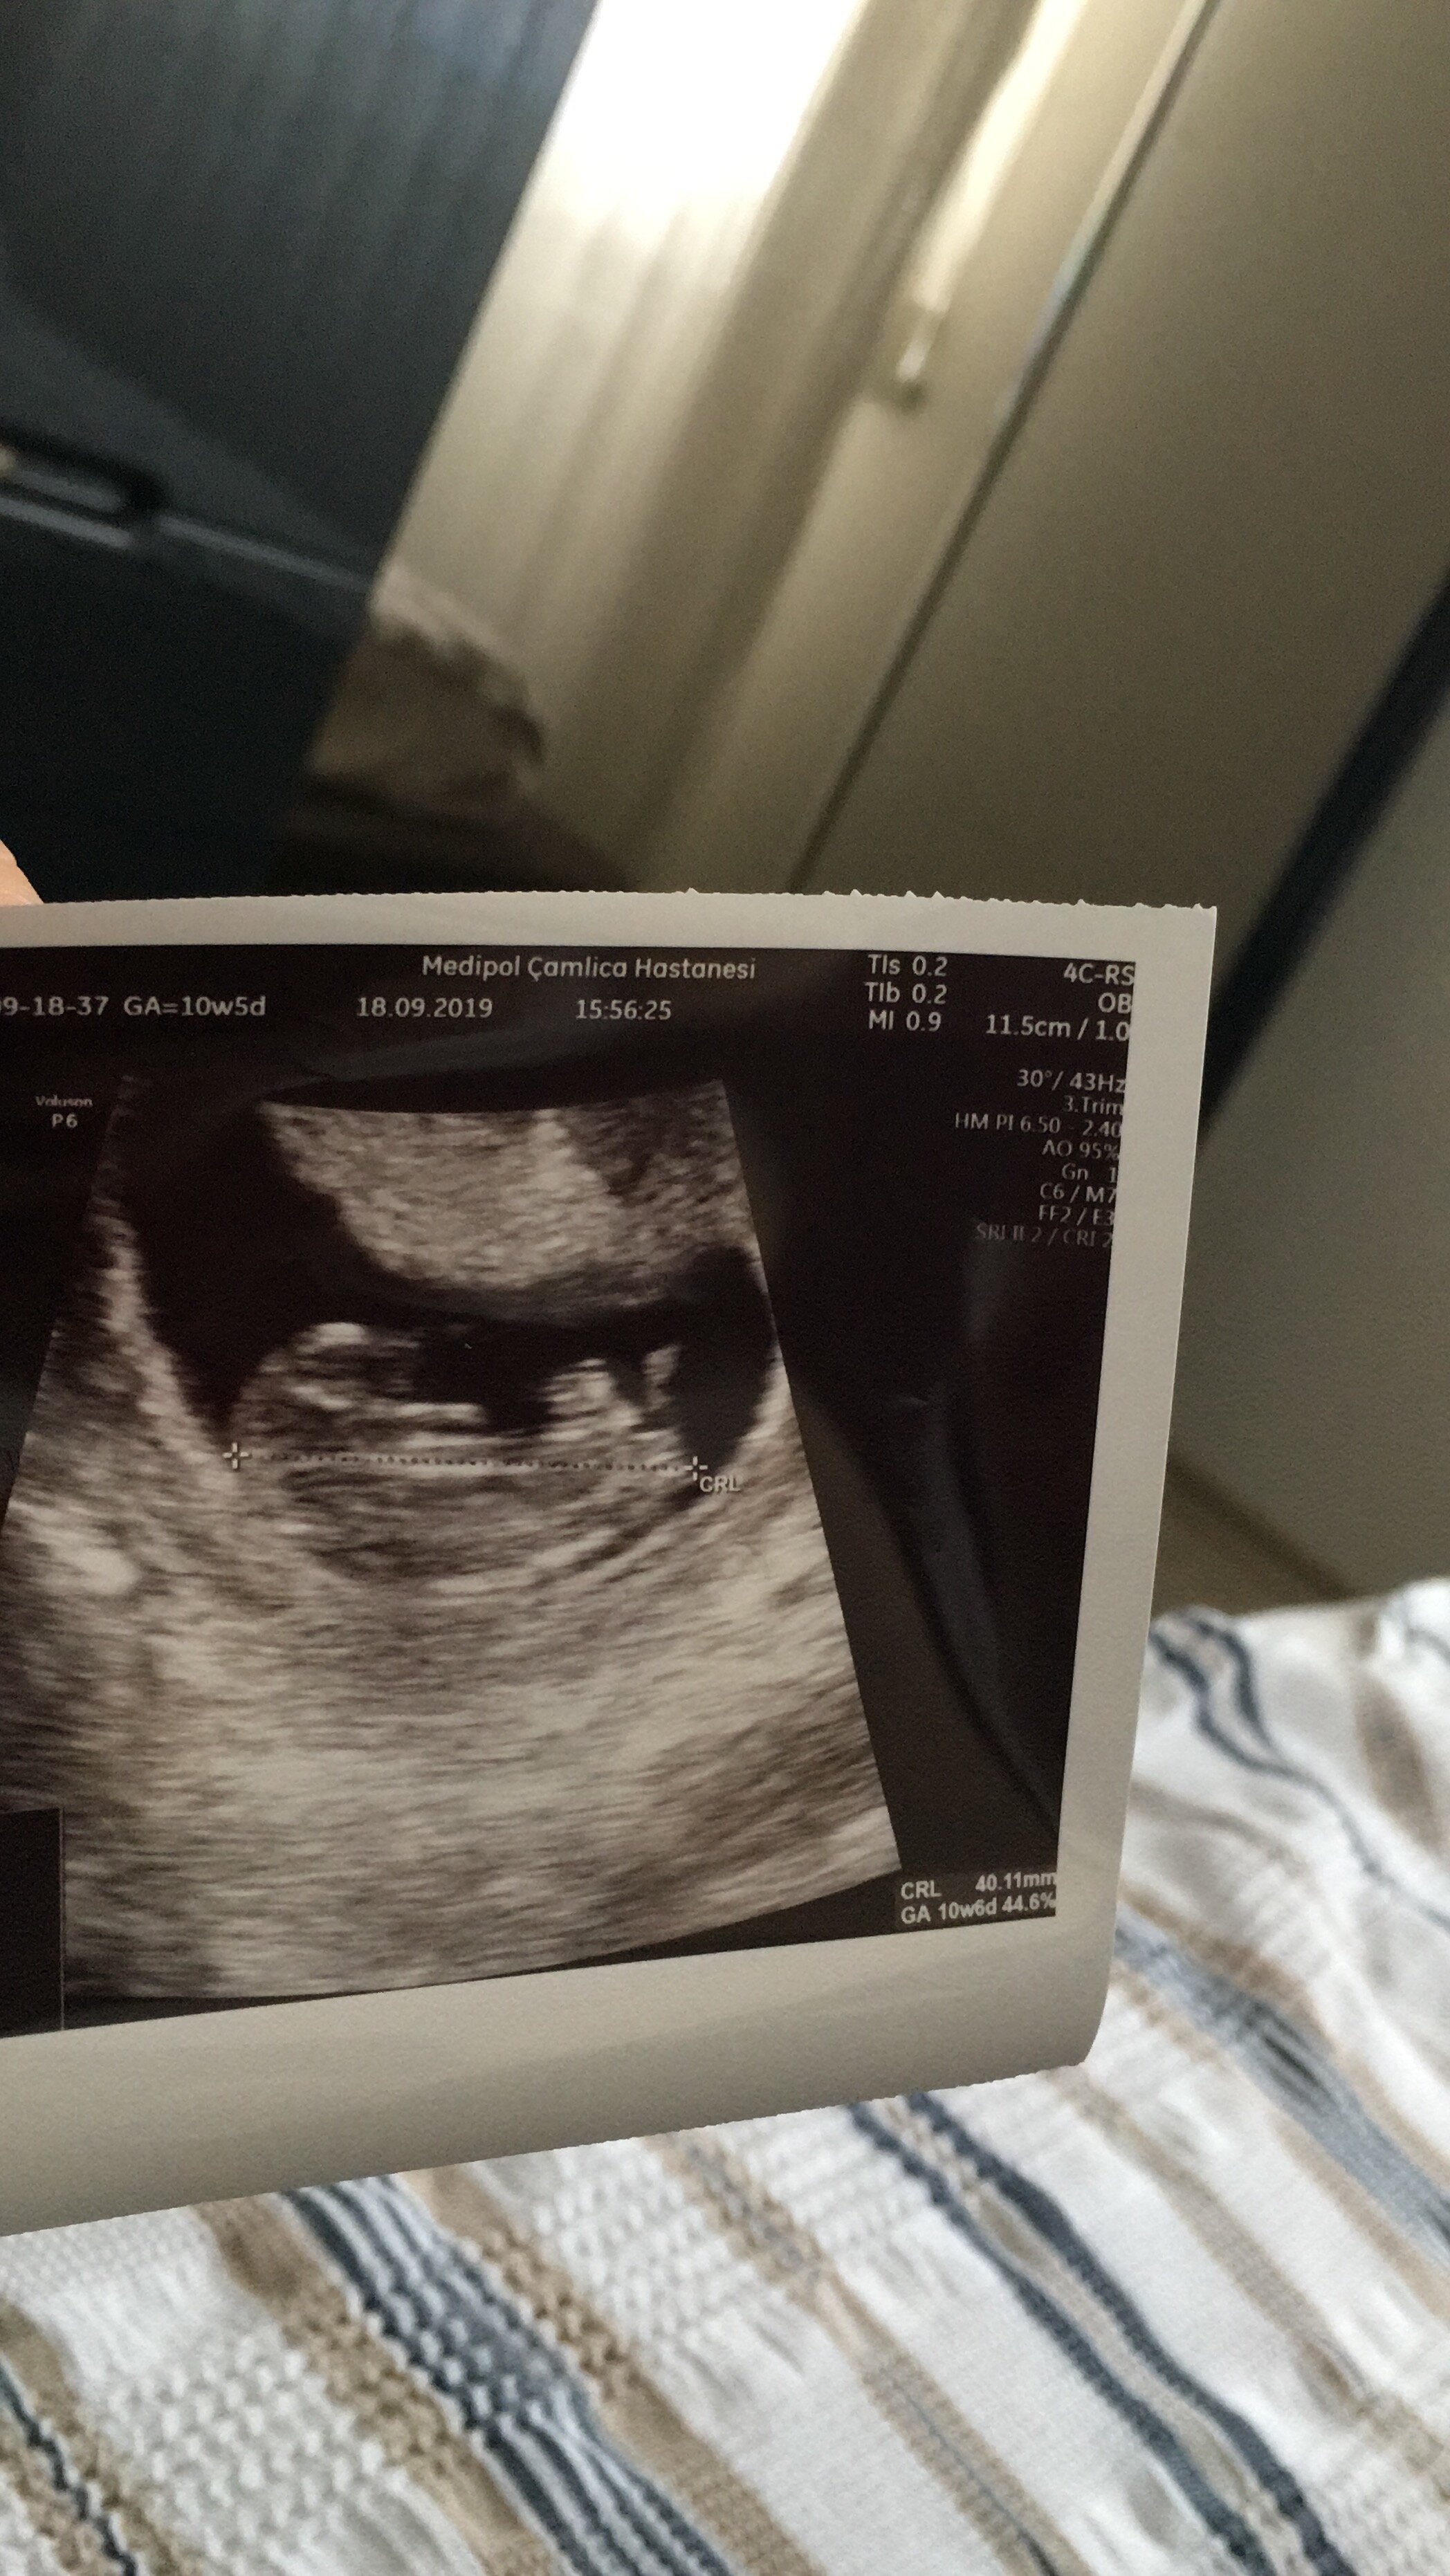

Ultrason sonucuna göre cinsiyet tahmini

MerhabLar.Lutfenn nub teoresi ile tahminde bulunun kizmi erkekmi sizce??

Merhaba banada tahminde bulunursanız çok mutlu olurum ♥️